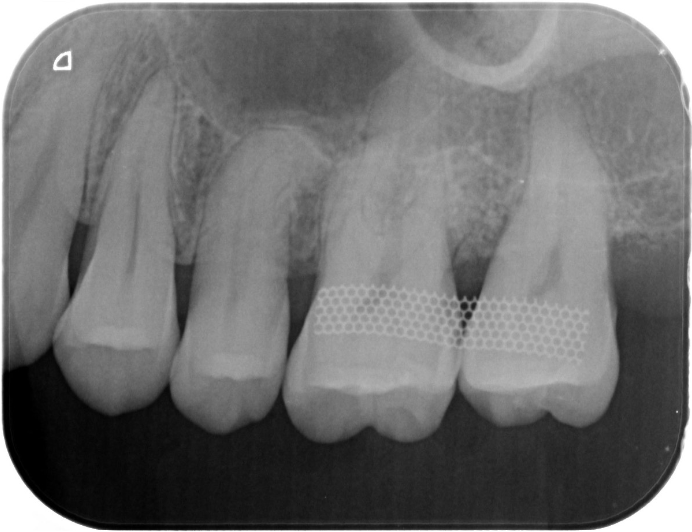

症例2

| 項目 | 詳細 |

|---|---|

| 患者様データ | 67歳 女性 |

| 来院時の主訴 | 「歯周病を治して一生自分の歯で食事を摂りたい。」 |

| 医院の診断 | 重度歯周病とう蝕 |

| 通院期間 |

1年6ヶ月 |

| 来院回数 | 10回 |

| 治療費 | 総額:480,000円(税抜) 歯周基本治療は保険適用診療 【内訳】 《保険適用診療》 歯周病検査・歯磨きや生活習慣指導・歯石取りクリーニング 《自費診療》 歯周組織再生療法240,000円(費用は範囲によって異なります。)、セラミック治療120,000円×2 |

| リスクと副作用 | メインテナンスが必要、正しい歯磨き習慣が必要不可欠 |

| ここがこだわりのポイント!☝ | 重度の歯周病の治療には長い治療期間がかかります。重症になるまでに時間がかかっている分、治るのにも時間がかかるからです。この症例の場合、患者様に頑張っていただいた結果、歯周ポケットが8mm→2mmに改善し、健康な歯周組織(骨・歯肉)を獲得することができました。 一生涯自分の歯で食事ができるよう、引き続きサポートを続けさせて頂きます!本当によく頑張って下さいました。お疲れ様でした! |